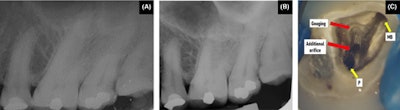

(A, B) The preoperative intraoral x-ray of the man’s maxillary left second molar. (C) Pulp chamber floor of the tooth showing the presence of an additional orifice in close approximation relation to the palatal (P) orifice and subsequent gouging in the distobuccal region adjacent to the mesiobuccal (MB) orifice.Images courtesy of Marya et al. Licensed by CC BY 4.0.

The patient’s pulp chamber floor was examined with an endodontic explorer, which revealed three distinct root canal orifices: the mesiobuccal, palatal, and another orifice in close approximation to the palatal canal. It appeared that there was an extra palatal canal. While attempting to search for the distobuccal canal in its usual position, the floor in that area was gouged, they wrote.